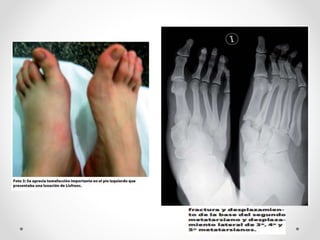

Este documento describe la articulación tarsometatarsiana, también conocida como articulación de Lisfranc. Explica que está formada por una serie de articulaciones sinoviales entre los huesos tarsianos (cuneiformes y cuboides) y los huesos metatarsianos. También detalla los mecanismos de lesión, incluidos los directos e indirectos, y los medios de unión entre los huesos, como las cápsulas articulares y los ligamentos interóseos, dorsales y plantares.